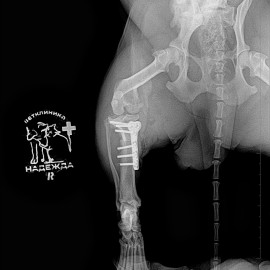

Наш пациент собака породы джек-рассел-терьер по кличке Эльза. Обратились с жалобами на остро развившуюся хромоту на правую заднюю конечность. После проведенных исследований был поставлен диагноз: разрыв передней крестообразной связки правого коленного сустава. Была проведена операция: TPLO.

Снимок 2 после операции.